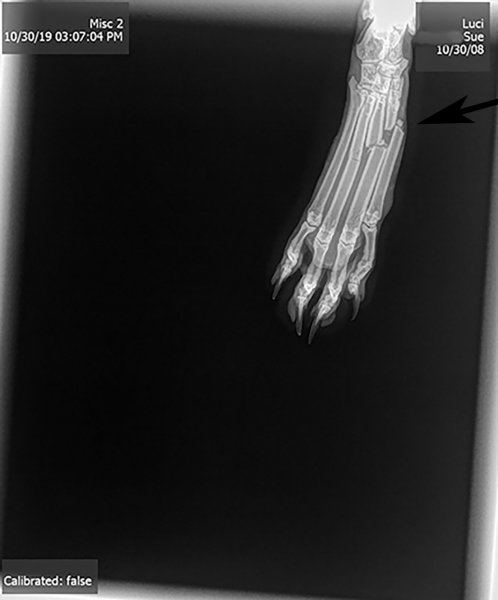

On October 30, we were preparing to drive to Florida, so I'd lowered the blinds on her favorite window - she didn't realize this (I think??) and jumped up there to have a look out - something about her landing didn't work as planned and I heard a crash (From upstairs)...went down to see what had broken and there wasn't anything except Luci there - resting nearby - looking at me as if 'what???' - I asked her what had happened...and noticed her limping away - up the stairs - I went after her and brought her back downstairs and noticed that her foot seemed to be bothering her - a lot - it looked puffed up to me - I called the vet and they said to bring her in - I rushed her right on over there - they said she'd need sedation to x-ray her foot - and that's when they reported that 3 of the 4 bones were broken...two were completely out of alignment...so they said she'd need a cast and pain meds - 6-8 weeks with no running or jumping, etc. right...

Here's a pic of her x-ray from that day:

Luci_x-ray-copy-with arrow.jpg

Luci had her vet visit and he said the x-rays revealed that she is healing - but she's not there yet - so next appointment is for Jan 6 - and hopefully that will be 'the day' for cast removal...I think a celebration will be in order!